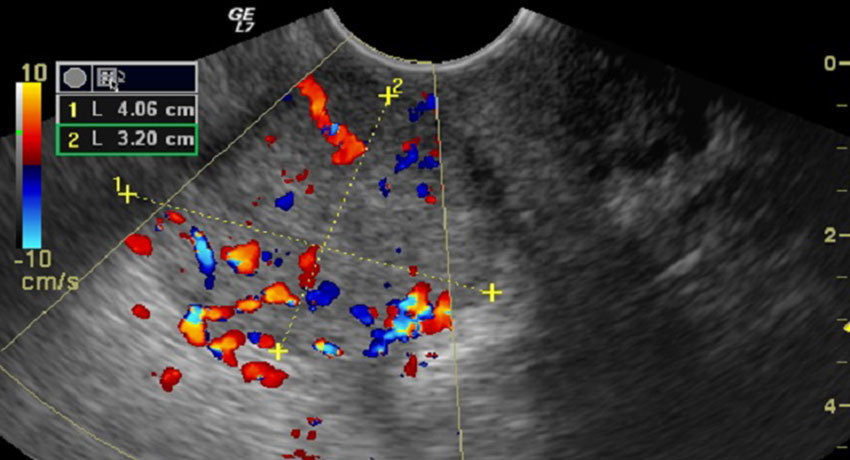

Степень распространения рака в организме и его стадию определяют с помощью компьютерной томографии, МРТ. Вторичные очаги помогает обнаружить рентгенография костей, грудной клетки. Современный золотой стандарт в поиске метастазов — ПЭТ-сканирование. Во время этого исследования в организм вводят безопасное радиоактивное вещество, которое накапливается в раковых клетках и «подсвечивает» их на снимках, выполненных с помощью специального аппарата. Для того, чтобы лучше оценить расположение опухолевых очагов, совмещают снимки, выполненные с помощью ПЭТ и компьютерной томографии.